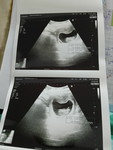

แม่น้ำหนักขึ้น4โล ท้องไม่ออกเลย วันนี้ไปซาวคุณหมอบอกน้องโตตามเกณฑ์เลยค่ะ

ไม่ออกเหมือนกันค่ะแม่ แต่ตอนพบคุณหมอ ก็บอกว่าน้องแข็งแรมตามเกณฑ์ค่ะ